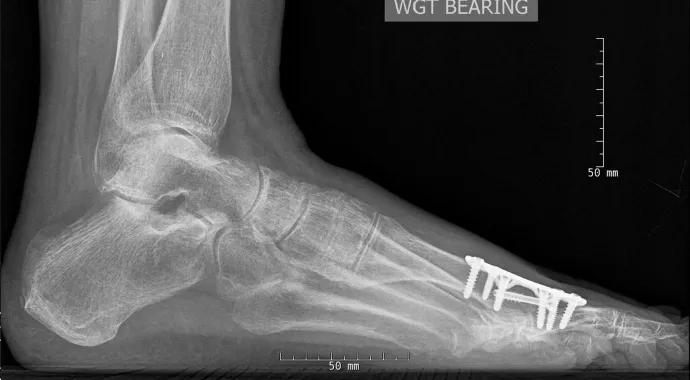

Figures  Preoperative anteroposterior and lateral weight-bearing X-ray views of a 54-year-old woman with a five-year history of right first MTP joint pain. Hemiarthroplasty and metatarsal osteotomy were performed 10 years earlier.

Preoperative anteroposterior and lateral weight-bearing X-ray views of a 54-year-old woman with a five-year history of right first MTP joint pain. Hemiarthroplasty and metatarsal osteotomy were performed 10 years earlier.

Postoperative anteroposterior and lateral fluoroscopy images of the first MTP joint with the allograft and hardware in place.